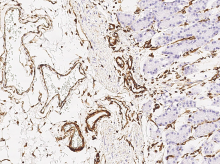

Anti-Vimentin antibody

(Cat#: 100254-R001)

Immunochemical staining of human Vimentin in human stomach. Image Credit: Sino Biological Inc.